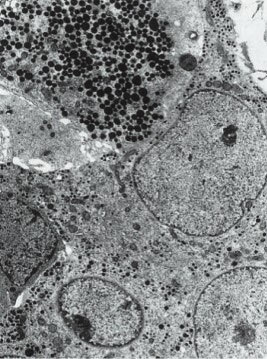

2.TSH细胞的解剖:TSH细胞约占垂体前叶细胞总数的5%,主要聚集于垂体前叶的前内侧(图4-2-1),其形态小于其他细胞类型,形状不规则且有细长的胞质突起(图4-2-2),细胞核呈圆形或卵圆形,胞浆内富含PAS-/AF-/AT+的分泌颗粒(图4-2-3)。免疫组织化学方法是光学显微镜下观察TSH细胞最可靠的方法,它不易被酸性染料和苏木精-伊红染色,相比于垂体促肾上腺激素细胞碱性染料和PAS着色浅。电镜下,促甲状腺细胞胞浆丰富,卵圆形细胞核位于细胞中央,粗面内质网上散在着很多囊泡。高尔基复合体聚集在核周,其形态随激素合成活性而变化。棒状结构的线粒体在电镜下呈电子致密团样结构,内部可见规则排布的横嵴。吞噬溶酶体多见。小球状的分泌颗粒直径为100nm至200nm不等,电子密度较小,分泌颗粒胞吐并不可见。

TSH分泌细胞电镜结构:胞浆内富含分泌颗粒 [10] 。

图4-2-3 TSH分泌细胞电镜结构:胞浆内富含分泌颗粒